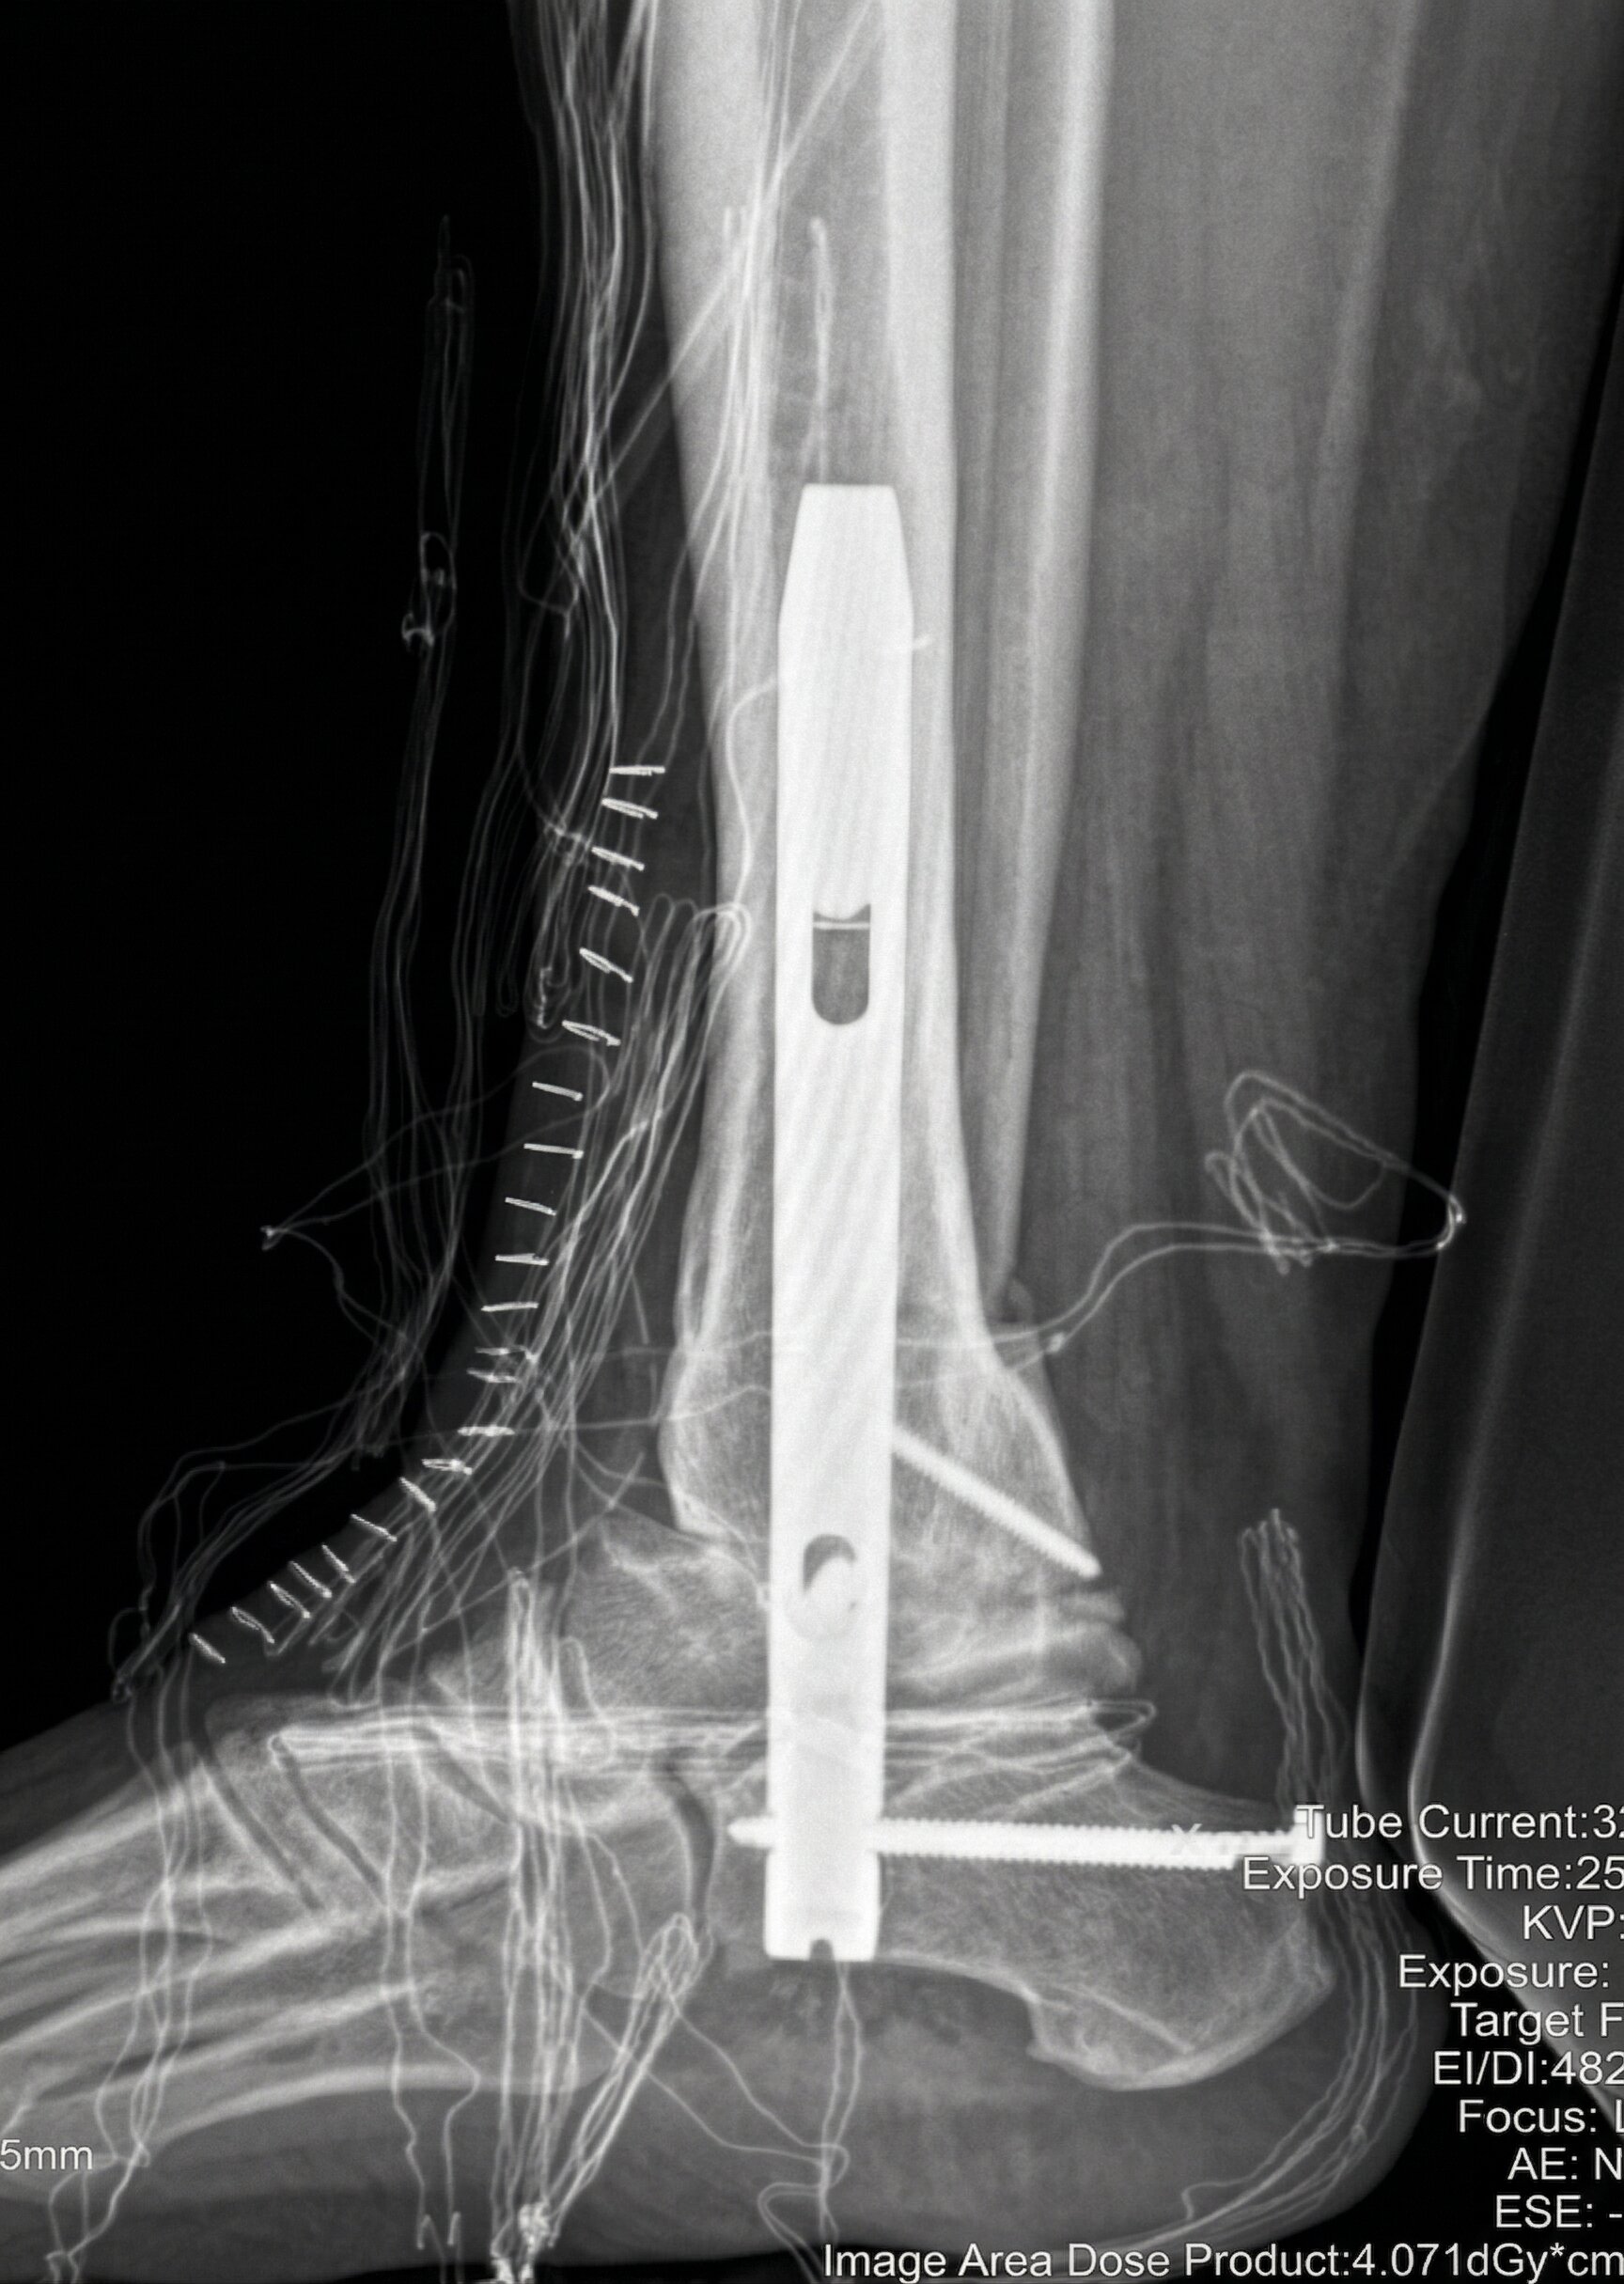

Artrosi di Caviglia

Condizione degenerativa spesso post-traumatica che provoca dolore durante il carico e limitazione del movimento.

Il trattamento varia da terapie conservative (infiltrazioni) a chirurgia per mezzo di protesi articolate o artrodesi (blocco della caviglia).

La protesi ha il beneficio di restituire il movimento, l’artrodesi quello di garantire una risoluzione definitiva del dolore.